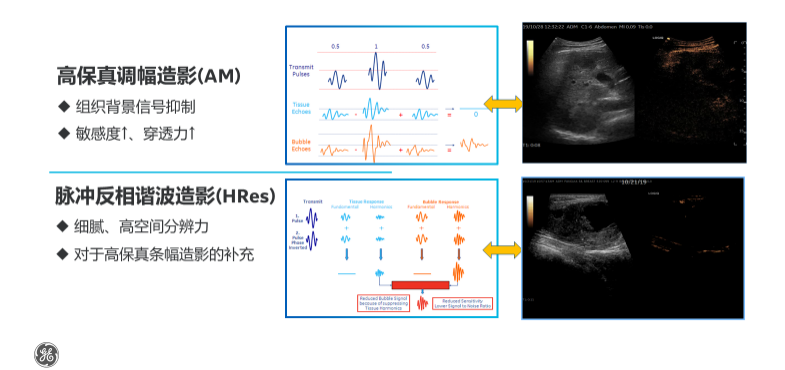

TCI动态空间聚焦技术是该设备的最大亮点,从精准成像到精准诊断,支持双模式造影成像及双造影剂设置,满足全身不同脏器组织造影需求;AI辅助工作流优化,有效缩短检查时间,提升诊断准确率;无辐射、无创检查,降低对患者身体的影响,显著提升就医体验感。